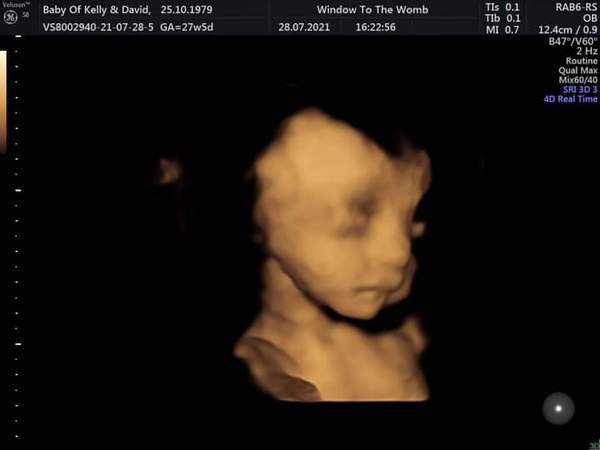

MumOfMiracles · 05/08/2021 12:01

Here is a pic of my girl at bonding scan. xx

@MumOfMiracles aww she's beautiful I'm pleased it's all going well. Considering my girl has edwards she's doing well, she has an exomphalos and a small vsd but other than that it's all good. Makes me glad I decided to continue 😌

Oh my goodness! She looks so precious! I hear you too, feels such a shock to be asked if you want to terminate your pregnancy, triggers all sorts of fears. So glad our girlie's are growing and going strong! Fighter for sure. Looks like your girl is so content and snuggly in there, bless her. Rooting for both our beautiful girls as we count down our last weeks. xx

Wow! Those pictures are fantastic @kellyd79 and @MumOfMiracles! They are so clear. It is amazing. I hope you are both doing OK.